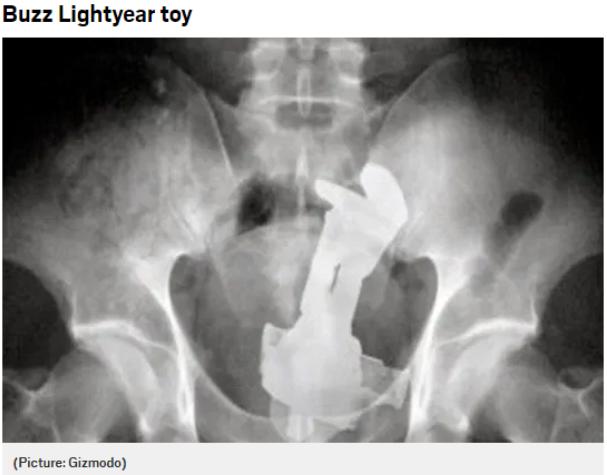

但是你以为这就结束了吗?no!